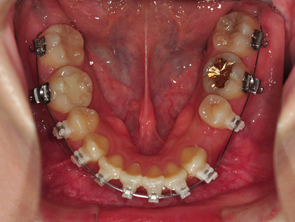

새로 갈아끼운 와이어는 2단계높인 와이어라고 설명해주셨어요 이 와이어는 입안 온도에서 더욱 효과가 잘 일어나는 와이어로 찬 온도에서 그 기능이 저하 될수 있기때문에 얼음물이나 차가운 음료는 많이 마시지 않는게 좋다고 말씀해주셨어요

2. 하악 스크류 진행

하악 스크류 진행은 사진에 위치와 각 위치에 대해 설명을 넣어놓은것처럼 앞부분에 스크류를 넣는것이 가장 이상적이지만 치아를 발치한 부분이어서 잇몸이 약해 스크류를 넣기 힘들수도 있다고 하시더라구요 ㅠㅠ 그래서 그다음으로 후보2번째 에 스크류를 넣을 수도 있고 만약 후보2번에 안된다면 입안쪽으로 후보3번 부분에 해야하는데 그쪽은 잇몸을 절제해서 스크류를 진행해야 한다고 하시면서 잇몸 건강하죠~~?? 하시는 의사 선생님 후엉!! 제발~!!!!! 후보1번에 스크류 할수있었으면 좋겠어요 ㅠㅠㅠ